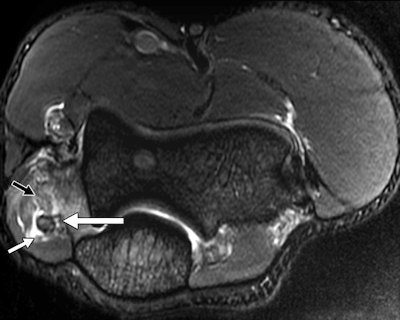

"Elbow injuries in Olympic sports have not been reported previously," noted lead author Dr. Sarath Bethapudi, from the department of musculoskeletal radiology at Leeds Teaching Hospitals National Health Service (NHS) Trust in the U.K. "Most of the injuries resulted from valgus strain with hyperextension of the elbow and usually presented as injuries to the medial joint supporting structures. Combinations of medial and lateral ligaments were seen in combat and power sports with high-energy acute trauma. Such injuries also resulted in tears to secondary stabilizers of the medial joint, including the common flexor tendons and medial muscular compartments" (AJR, September 2013, Vol. 201:3, pp. 535-539).

Of the 28 elbows scanned for acute sports injuries, 15 had high-grade ligament injuries, and 12 of these ligament injuries occurred in contact sports and weightlifting. The remaining three injuries were seen in throwing athletes, two of whom were javelin throwers and one of whom was a volleyball player.

"Tears of the common flexor and extensor tendons occurred in combination with ligamentous injuries. This occurs because common flexors and extensors act as secondary stabilizers of the elbow joint and are injured when the primary stabilizers fail. Once again, these injuries occurred primarily in combat sports, weightlifting, and overhead-throwing athletes," stated Bethapudi, who was responsible for data collection and analysis at the 2012 Olympics and has received funding from GE Healthcare, a sponsor at the games.

Significant ligament and tendon injuries to the elbow can occur often in nonthrowing athletes, and most of the elbow injuries seen in these athletes were isolated high-grade ulnar collateral ligament (UCL) injuries, although combinations of medial and lateral ligament injuries can occur, the authors concluded. Ulnar attachment tears were the next most common injuries, followed by midsubstance tears of the UCL. This trend differs from the existing literature, which suggests that midsubstance tears are the most common type of UCL injuries, they wrote.